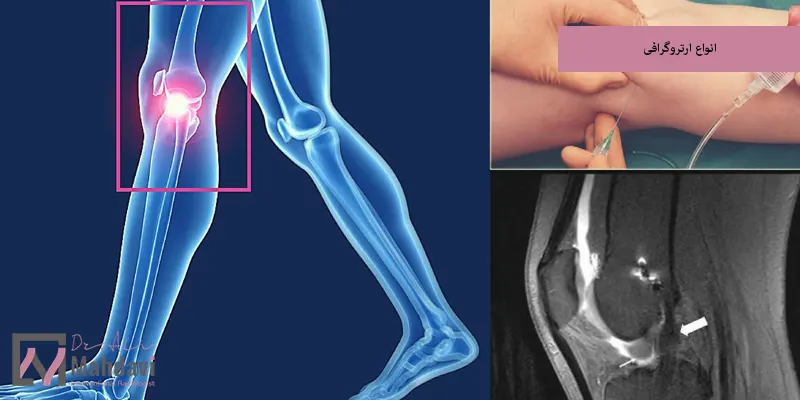

انواع ارتروگرافی

ارتروگرافی بسته به نوع فناوری تصویربرداری و هدف بررسی، به چند نوع مختلف تقسیم میشود و هر نوع از این روش ها مزایا و کاربردهای خاص خود را دارد:

در سیتی آرتروگرافی از سیتیاسکن پس از تزریق ماده حاجب استفاده میشود تا تصاویر سه بعدی و بسیار دقیقی از ساختارهای درونی مفصل تهیه شود و این نوع برای بررسی آسیب های ظریف در استخوان ها، غضروف ها و رباط ها کاربرد دارد و همچنین گزینه مناسبی برای افرادی است که به دلایل خاص نمیتوانند MRI انجام دهند.

امآر آرتروگرافی

در این نوع، پس از تزریق ماده حاجب مخصوص، از دستگاه MRI برای تصویربرداری استفاده میشود، امآر آرتروگرافی دقیق ترین نوع ارتروگرافی است و جزئیات بافت های نرم مانند رباط ها، غضروف ها و تاندون ها را با وضوح بالا نشان میدهد، این روش برای تشخیص آسیب های مفصل شانه، لگن و زانو به ویژه در ورزشکاران بسیار مؤثر است.

تزریق ماده حاجب به داخل مفصل

پس از آماده سازی، پزشک با استفاده از سوزن مخصوص و تحت هدایت تصویربرداری مانند فلوروسکوپی، مقدار مشخصی ماده حاجب را به درون مفصل تزریق میکند و این ماده باعث میشود جزئیات بافت های داخلی مفصل از جمله رباط ها، تاندون ها، غضروف ها و کپسول مفصلی با وضوح بیشتری در تصاویر مشخص میشوند و در برخی موارد ترکیبی از داروی بیحسی یا ضدالتهاب نیز تزریق میشود.